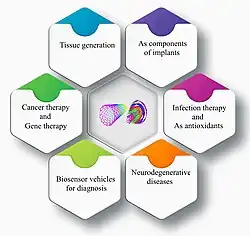

Biomedical Applications

Because of their relatively large surface area, CNTs are capable of interacting with a wide variety of therapeutic and diagnostic agents (drugs, genes, vaccines, antibodies, biosensors, etc.). This can be utilized to assist in drug delivery directly into cells.[196] In addition, CNTs have recently been used as reinforcements in implants and scaffolds due to their suitable reaction area, high elastic modulus, and load transfer capability.[197][198]

CNTs have been shown to increase the effectiveness of bioactive coatings for the attachment, proliferation, and differentiation of osteoblasts, and has been used as a bone substitution material.[199]

CNTs may be used as reinforcing materials for chitosan-containing coatings used on implants and medical scaffolds.[200]

Biosensing

Potential future applications include biomedical and environmental applications such as monitoring plant health in agriculture,[206][207][241] standoff process control in bioreactors, research/diagnostics of neuronal communication[242] and numerous diseases such as coagulation disorders,[243] diabetes,[221][244] cancer,[245] microbial and viral infections,[226][246] testing the efficacy of pharmaceuticals[247] or infection monitoring using smart implants. In industry, SWCNTs are already used as sensors in the detection of gases and odors in the form of an electronic nose[248] or in enzyme screening.[249]